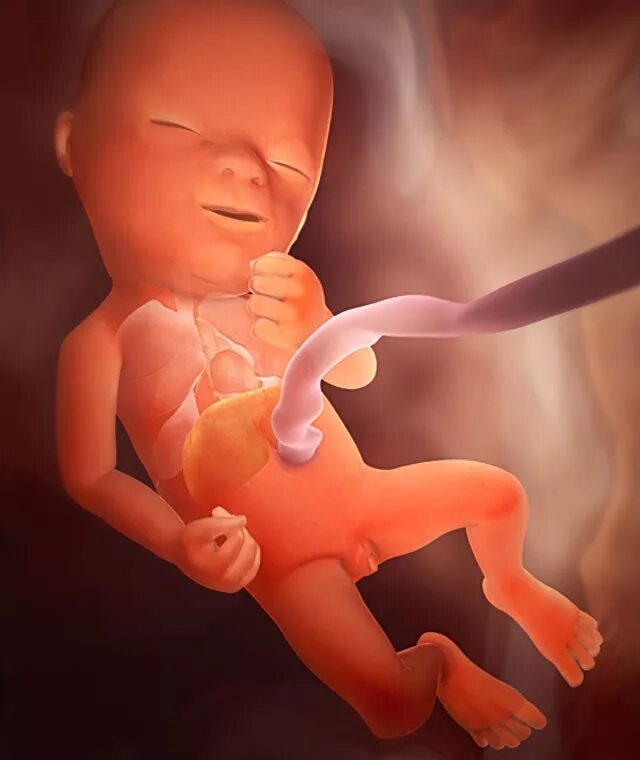

13 недель как выглядит малыш